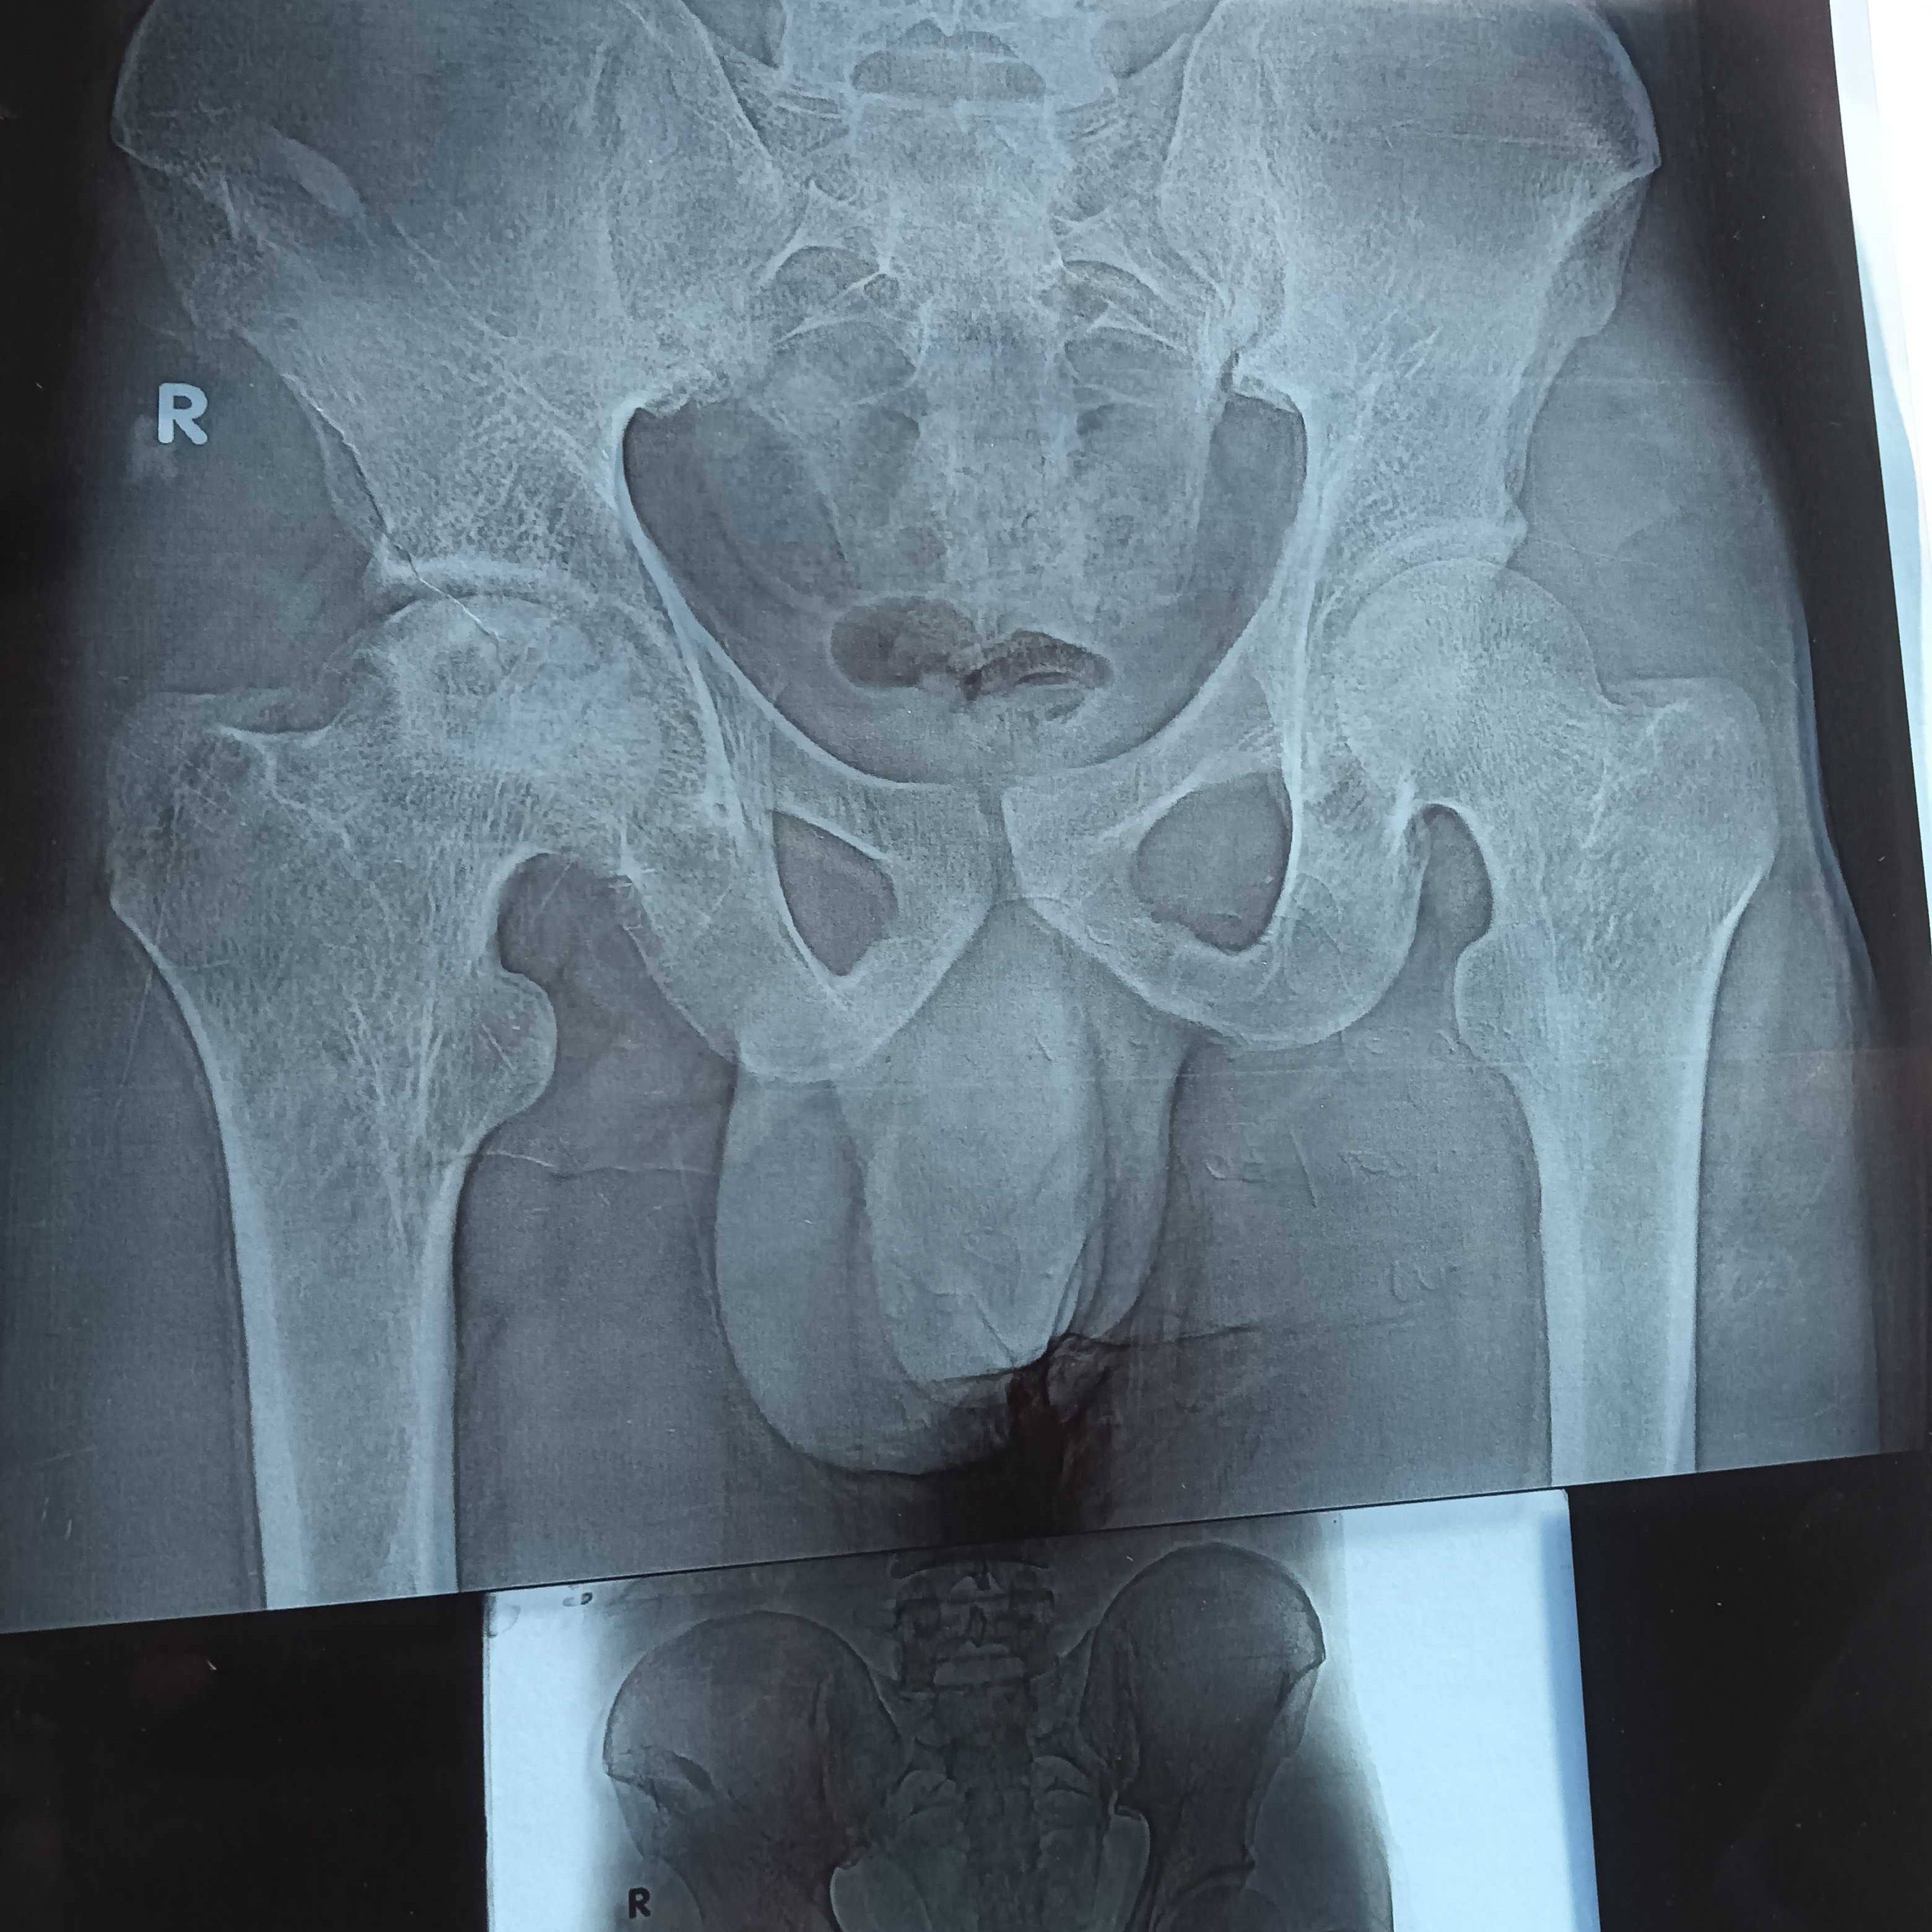

Dr Sir, AVN 3rd stage in both shoulders due to steroids used during COVID treatment and also having bilateral in hip joint 2nd and 3rd stage. 1. Can undergo bilateral hip replacement 2. How to manage with a paining shoulder after hip replacement 3. Or need treatment for shoulders first after sometime for the hips..